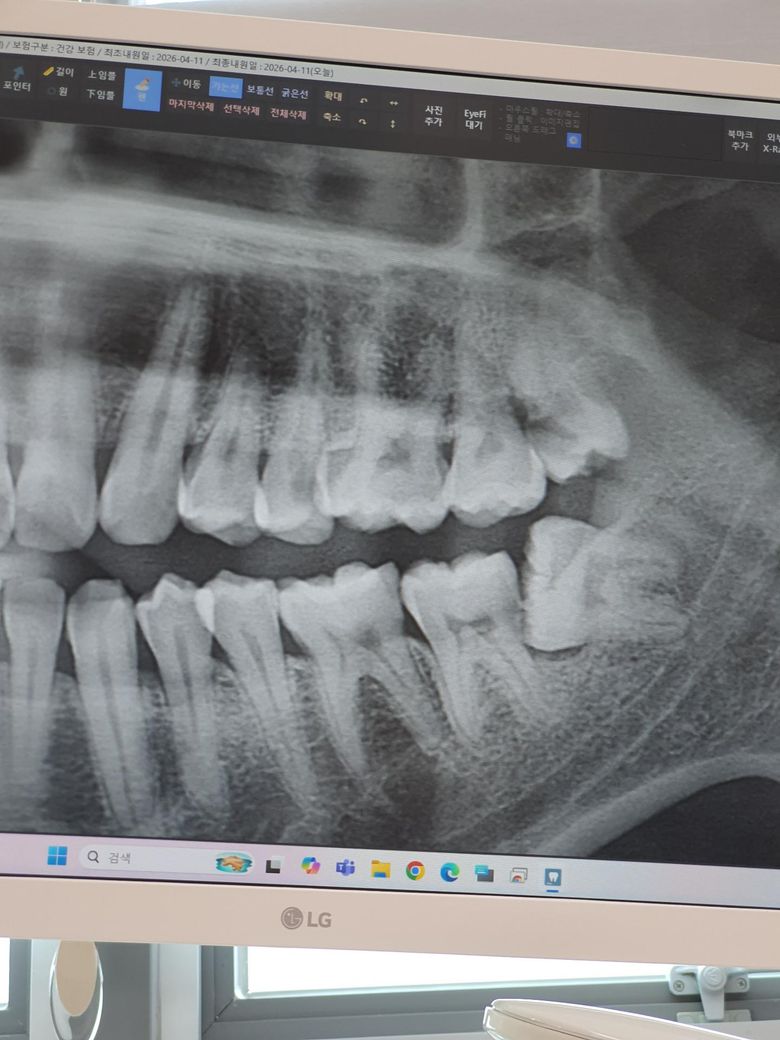

정기검짐으로 충치검사를 했습니다. 위쪽 표시된 부분에 충치가 있는건가요. 치과의사마다 의견이 다릅니다. 아프거나 시리지는 않습니다

사진만으로 100% 진단을 내리기는 원래 어렵습니다.

육안으로 보는 것과 함께 합쳐져야 정확한 진단이 완성되지요.

그럼에도 불구하고 아래 위 치아 2개다 충치가 있을 가능성이 매우 높아 보입니다.

위 치아는 육안으로 충치가 있는지 보일테고, 아래 경우에도 사랑니를 발치하고 육안으로 확인 후 치료를 진행해야 될 것 같습니다.

사진상으로는 표시한 부분이 충치가 맞는거 같습니다. 더 정확한건 작은 엑스레이사진을 찍어보고 아래쪽은 사랑니 발치를 하고나서 다시 확인 해보시는게 좋을것같습니다.

파노라마 엑스레이 사진은 겹쳐서 인접면 충치를 정확히 진단하기는 어렵고요 치근단 사진을 찍어보면 좋을 것 같습니다 충치가 의심되는 상황은 맞습니다